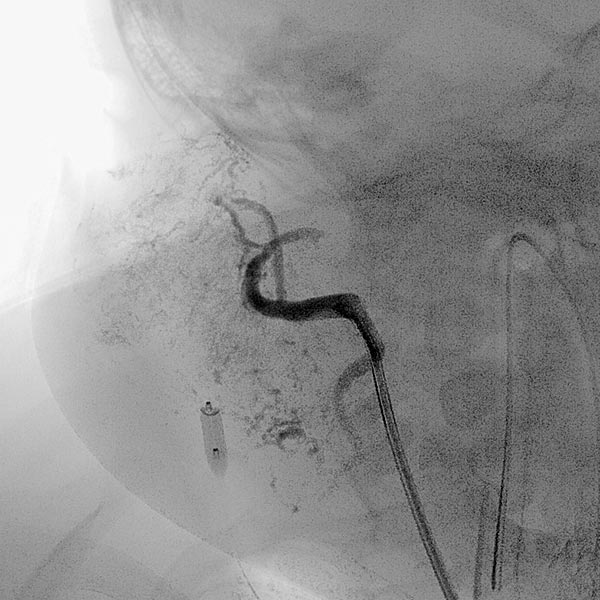

Digital subtraction angiography (DSA) after injection into the right common carotid artery shows the infantile hemangioma mainly supplied from the external carotid artery, as expected.

Digital subtraction angiography (DSA): After insertion of a 4F diagnostic catheter transarterially into the external carotid artery, selective advancement of a microcatheter into the maxillary artery. The infantile hemangioma presents as typical contrast pooling (“tumor blush”). The transvenously inserted balloon blocks the venous outflow and is clearly visible. Embolization was then carried out with particles of 150 micron size and without unintended venous outflow.